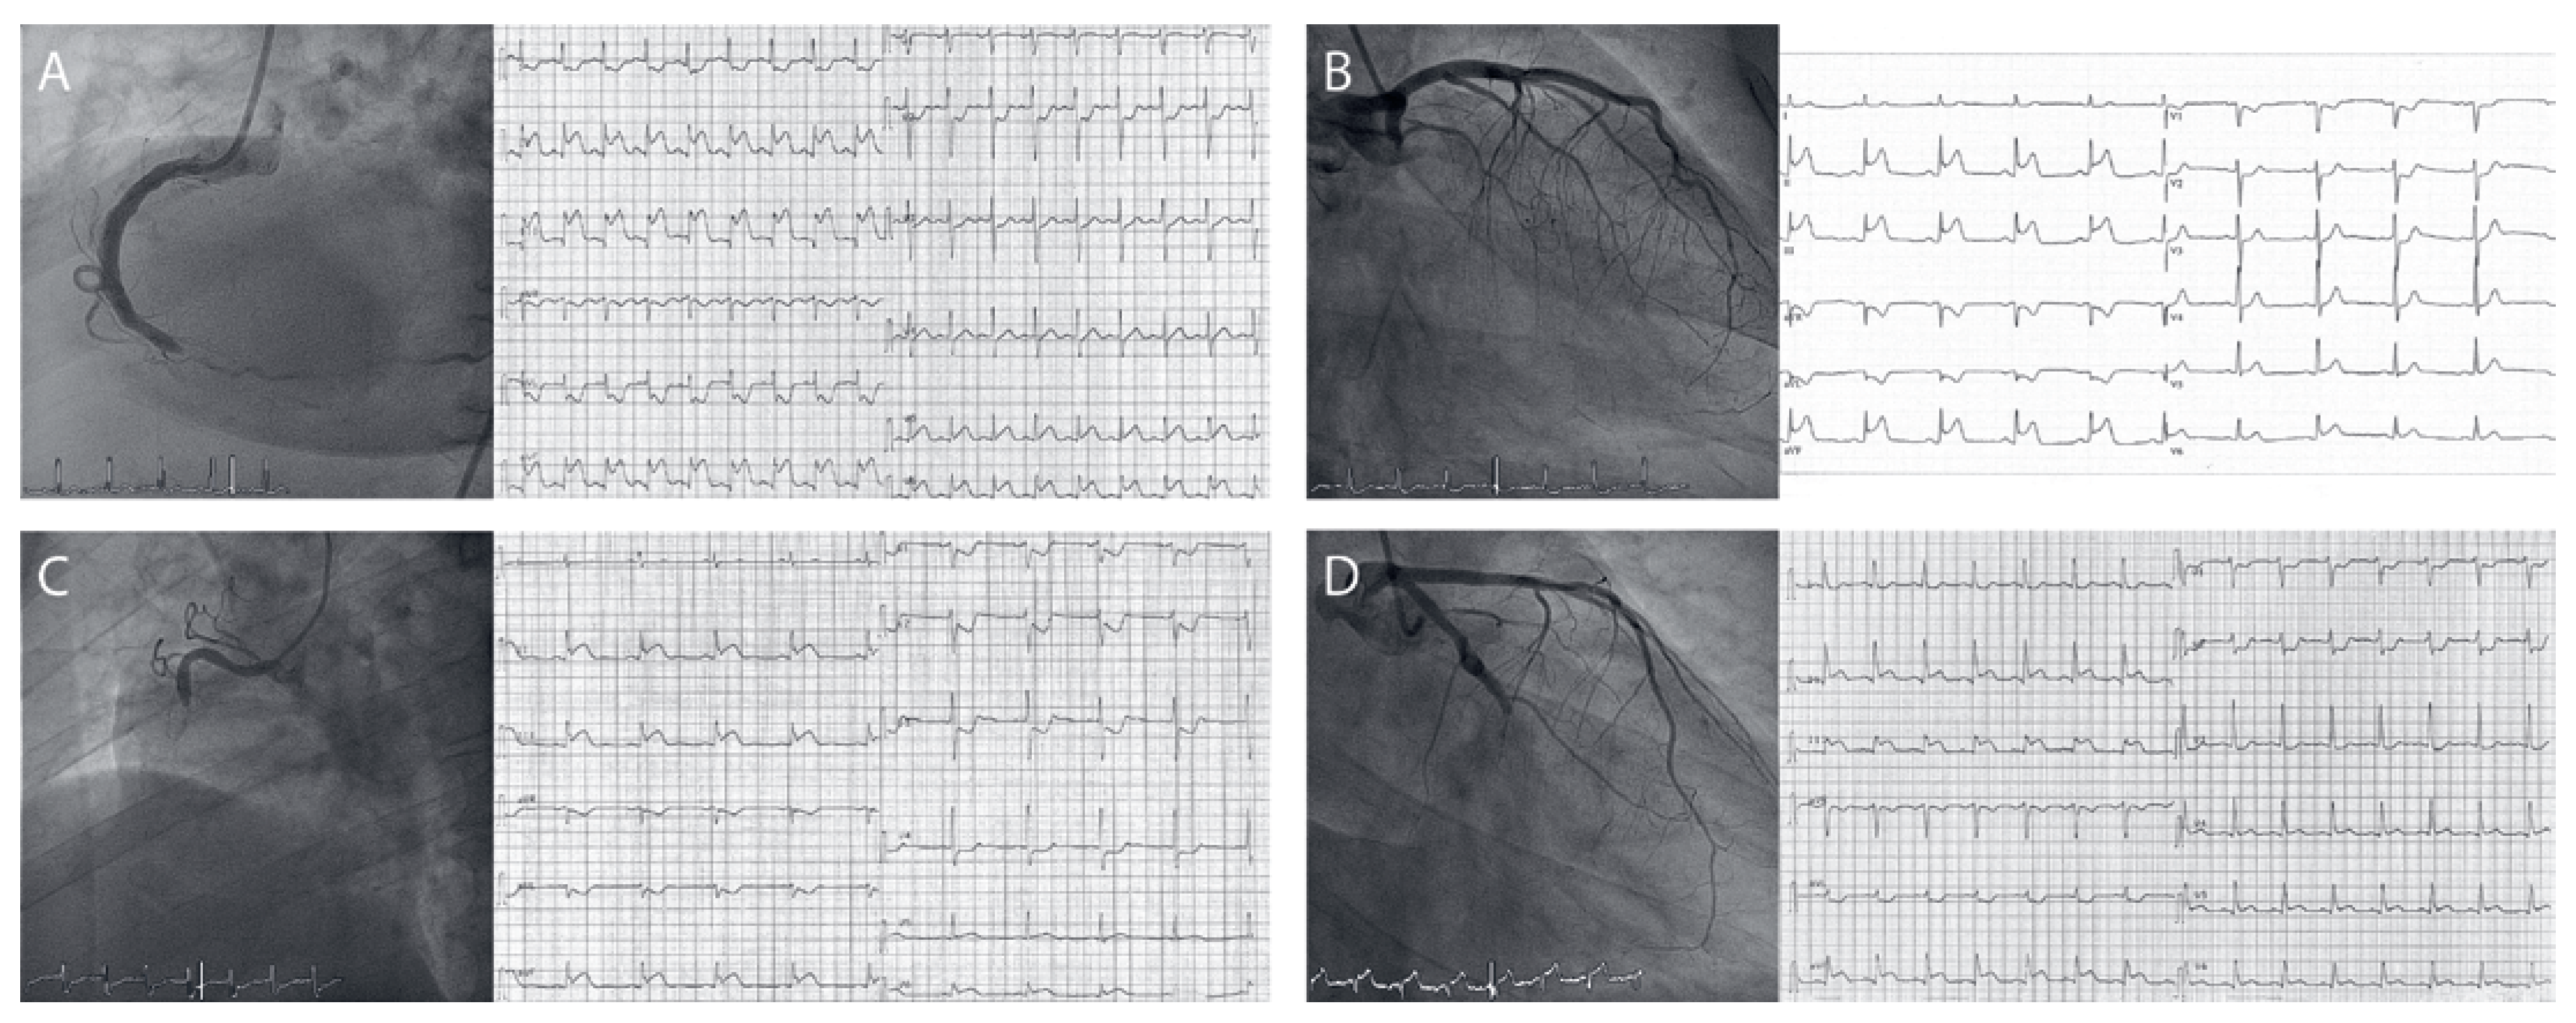

Figure 1. Examples of coronary angiograms and corresponding ECGs in patients with acute inferior ST-segment elevation myocardial infarction (STEMI). A positive ECG algorithm is defined as a ratio of ST-segment elevation in lead III:II of >1 and ST-segment depression in leads I and/or aVL >1 mm under baseline. A) Acute inferior STEMI due to occlusion of the distal right coronary artery (RCA) with a true-positive ECG algorithm. B) Acute inferior STEMI due to occlusion of the proximal left circumflex coronary artery (LCX) with a true-negative ECG algorithm. C) Acute inferior STEMI due to occlusion of the mid RCA with a false-negative ECG algorithm. D) Acute inferior STEMI due to occlusion of the mid LCX with a false-positive ECG algorithm.